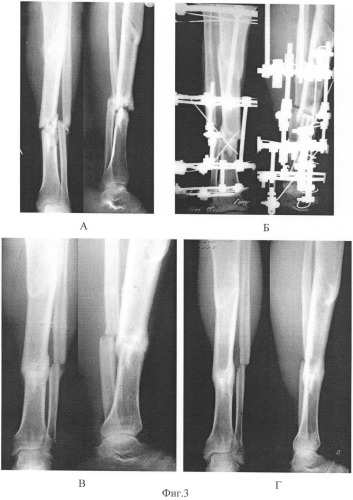

Мы сообщаем о случае неврологического осложнения, связанного с остеопоротическим переломом позвонка. 79-летняя женщина обратилась с жалобой на усиление корешковой боли в левой нижней конечности в течение 2 месяцев. В анамнезе у нее не было травм, и боль была наиболее сильной в левой ягодице, распространяясь вдоль левой задней части бедра и передней ноги. Она испытывала постоянную корешковую боль и дизетезию (иглы) в дерматоме L5 левой ноги в положении стоя, но почти не болела в положении на спине.Ее корешковая боль недавно усилилась в течение 10 дней, прежде чем она была госпитализирована. Когда она вставала или ходила, корешковая боль становилась сильной, что делало невозможным непрерывную ходьбу более 10-15 минут.

На вопрос о прошлых событиях, которые могли быть связаны с компрессионным переломом позвоночника, она вспомнила, что пережила один единственный эпизод острой и сильной боли в пояснице во время приступа кашля, связанного с вирусным бронхитом. Этот эпизод произошел за 2 недели до появления корешковой боли.

При неврологическом обследовании выявлена умеренная гипестезия дерматома L5. Рефлексы глубоких сухожилий в норме. Обследование также выявило умеренную двустороннюю боль в пояснице. Рост 160 см, вес 57 кг; она не принимала никаких регулярных лекарств, и в остальном была в хорошей форме. На рентгенограмме сбоку виден остеопоротический компрессионный перелом тела L5 позвонка. Магнитно-резонансная томография (МРТ) выявила отек, связанный с переломом, в виде сигнала высокой интенсивности на чувствительных к жидкости последовательностях.Компрессионный перелом тела L5 позвонка возник с линейно низкой интенсивностью сигнала на всех последовательностях. Компьютерная томография (КТ) позвоночного канала показала полный остеопоротический коллапс тела позвонка L5 (рис. 1). Он также выявил типичные признаки существовавшего ранее поясничного стеноза с гипертрофией желтой связки и двустороннего артрита и гипертрофии фасеточно-суставных суставов на уровнях L3, L4 и L5. Двустороннее сужение фораминалов выявлено на уровне L5. По данным денситометрии поясничной кости Т-балл составил -3,5.В анамнезе не было остеопоротических переломов. Остеопороз был диагностирован за несколько лет до этого и лечился бисфофонатами (ризедронатом в течение нескольких месяцев и золедроновой кислотой в виде одной инъекции за год до этого).

Рисунок 1.Компьютерная томография позвоночного канала показывает полный остеопоротический коллапс тела позвонка L5.

Операция была проведена через несколько дней после поступления в наше учреждение. Выполнена L5-ламинэктомия и двусторонняя фораминальная декомпрессия L5-S1.В первый послеоперационный день больной был мобилизован и начал ходить на костылях. Ее левая корешковая боль немедленно исчезла, хотя умеренная боль в спине осталась после 5-месячного наблюдения, но она не сообщала о рецидивирующей корешковой боли.

Уменьшение костной массы из-за остеопороза увеличивает риск переломов позвонков, которые в большинстве случаев лечат нехирургическими методами. 1 . Компрессия спинного мозга или корешка в результате остеопоротических переломов позвоночника является редким осложнением 2 .Остеопоротические переломы позвонков обычно представляют собой болезненные клиновидно-компрессионные переломы без неврологических симптомов, поскольку средний столб позвоночника не поврежден. И наоборот, при взрывных переломах, как в нашем случае, задействован средний столбик, и фрагменты кости могут вызывать сдавление нервных структур сзади или сбоку. Потеря высоты тела позвонка также способствует уменьшению диаметра межпозвонковых отверстий, добавляя к механизму компрессии корня. Дополнительные предсуществующие факторы, такие как выпуклость межпозвоночного диска, грыжа диска или стеноз поясничного канала, могут способствовать уменьшению диаметра позвоночного канала и сужению фораминального канала.У нашего пациента был стеноз легкой степени и фасеточный артрит, которые способствовали декомпенсации сужения фораминального отверстия и компрессии корня L5 после коллапса тела позвонка. Неврологические последствия могут значительно варьироваться в зависимости от уровня позвоночного коллапса: он может вызывать параплегию в случае компрессии спинного мозга на грудном уровне, синдром конского хвоста или изолированную радикулопатию в случае компрессии нервного корешка 3 .